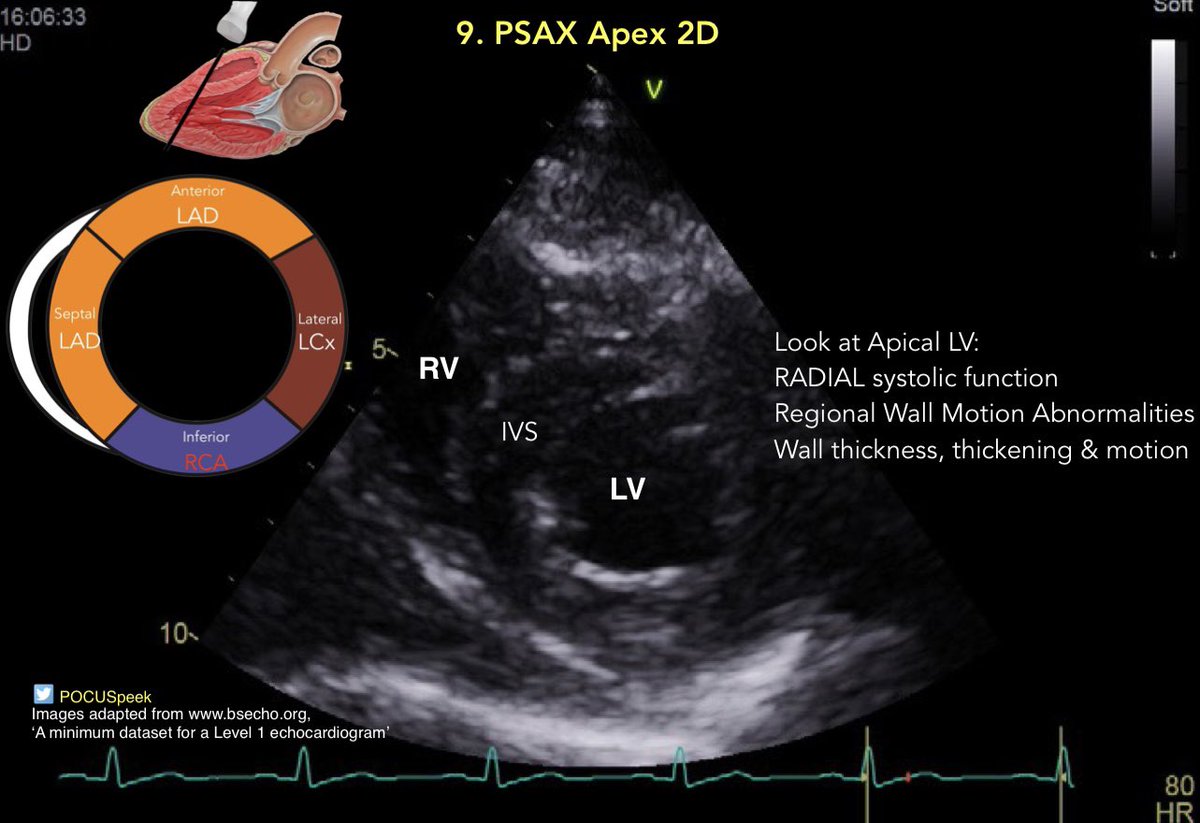

Some annotated #firstecho #POCUS main views 👇🏻 3/3